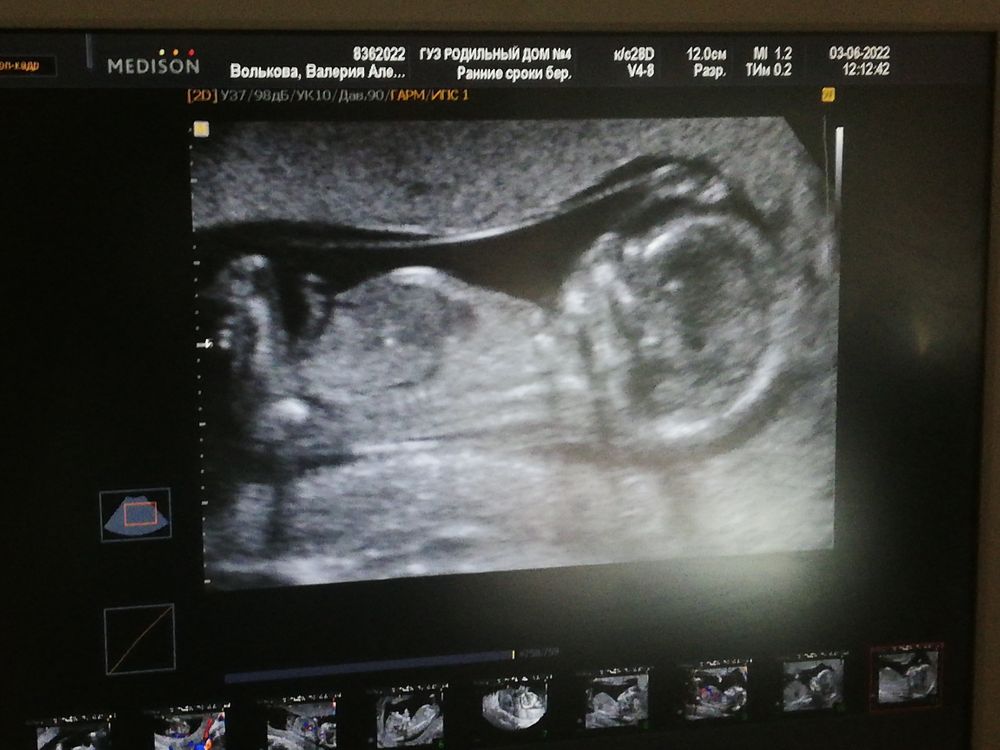

Ну что, первый скрининг пройден)) Как сказали, всё в норме, и соответствует сроку 13 недель и 3 дня. ЧСС - 158 КТР 78мм ТВП 1,6мм. Фотографию не распечатали, но разрешили сфоткать. Предположили мальчика) А вы как думаете, кто?)

На фото не видно половой бугорок)) Не знаю, откуда предыдущие комментаторы взяли, что мальчик. Но раз узист предположил, то, значит, он, возможно, разбирается в половых бугорках.